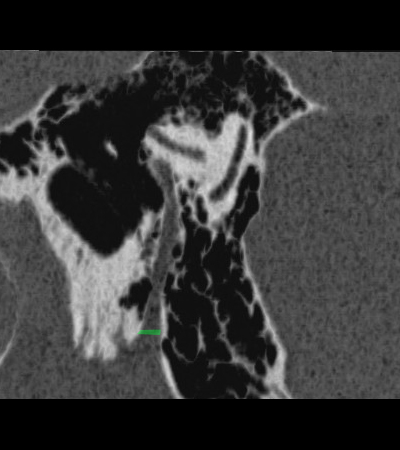

Radioanatomy of Temporal bone

Sagittal cut through the mastoid segment of facial nerve. Minimum Intensity Projection reconstruction.